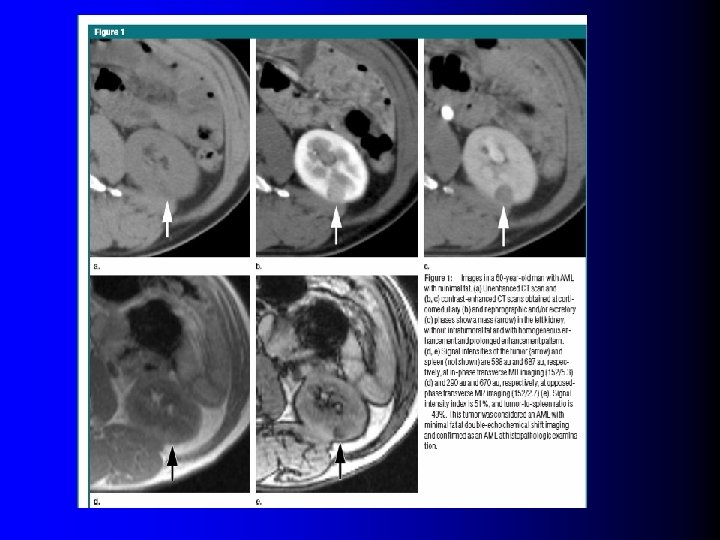

En résumé… l Portrait robot de l'AML – Echo: isoéchogène – TDM: sans graisse: Spontanément hyperdense l Sans calcification l Rehaussement homogène et en plateau l – IRM: l Chute du signal en opposition de phase – Si contingent graisseux pas trop faible !!! Diagnostic diff: Tubulo-papillaire !

En résumé… l Portrait robot de l'AML – Echo: isoéchogène – TDM: sans graisse: Spontanément hyperdense l Sans calcification l Rehaussement homogène et en plateau l – IRM: l Chute du signal en opposition de phase – Si contingent graisseux pas trop faible !!! Diagnostic diff: Tubulo-papillaire !